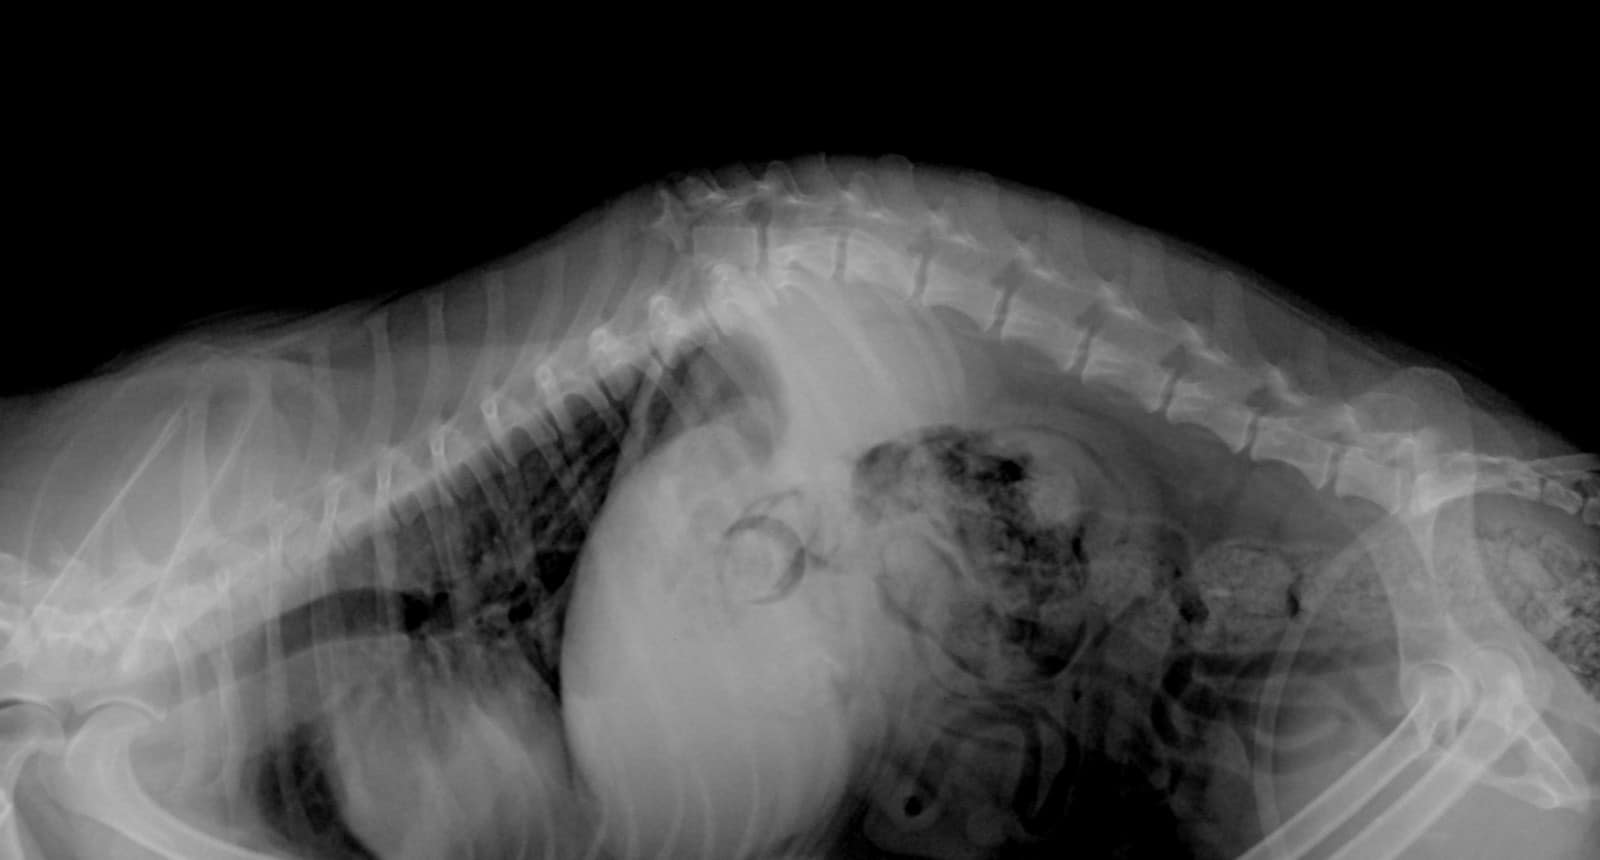

Все произошло в конце декабря прошлого года. Собачка Кнопа гуляла на самовыгуле и ее, видимо случайно, сбил на авто хозяин. У бедолаги был сломан позвоночник, но она доползла к людям в надежде, что ей помогут. Однако лечить Кнопу никто не собирался.

У Крохи сломан позвоночник / фото: fb ПРИЮТ для животных "ДРУГ " ДнепрУ Крохи сломан позвоночник / фото: fb ПРИЮТ для животных "ДРУГ " Днепр

Как пишут волонтеры приюта "Друг", хозяева принесли собаку в ветклинику и, узнав о сломанном позвоночнике, решили усыпить.